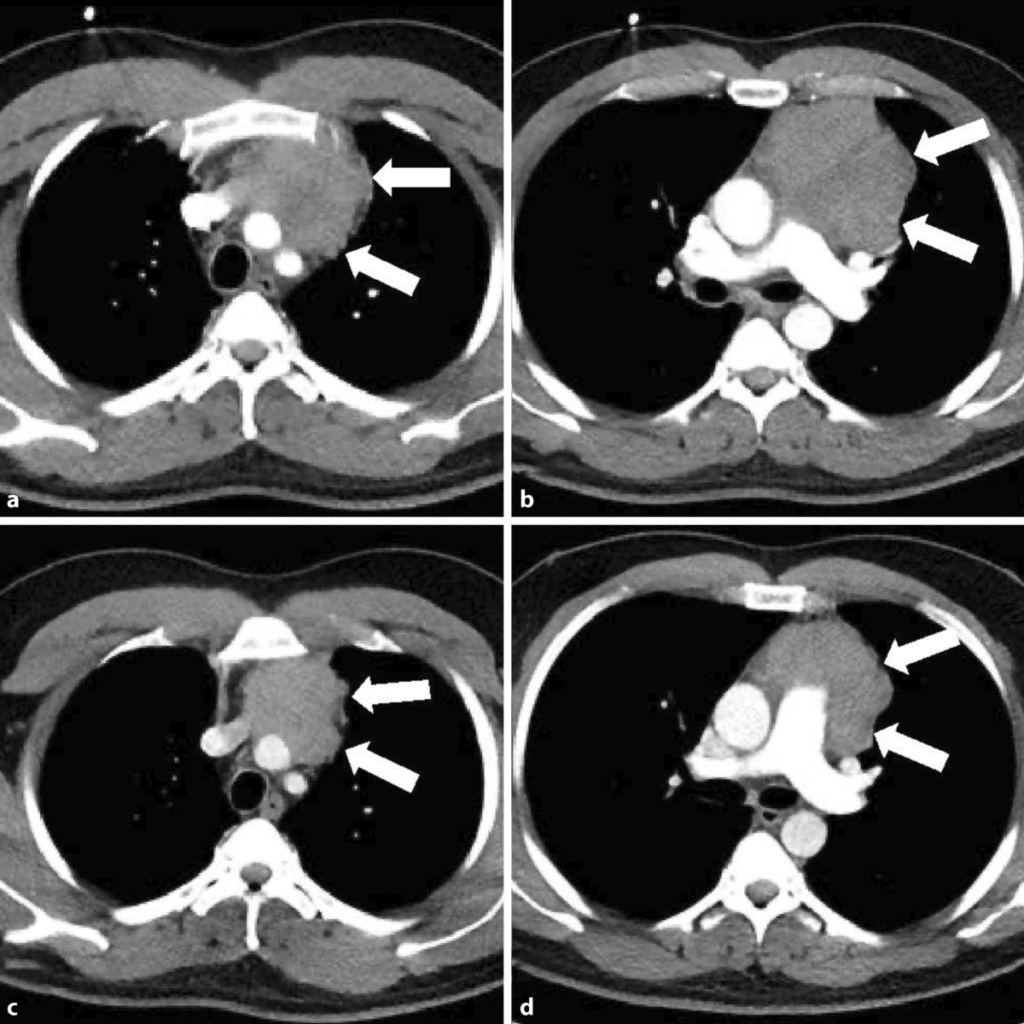

| Klinik: schmerzlose Lymphknoten (zervikal, mediastinal) B-Symptome (Fieber, Nachtschweiß, Gewichtsverlust) Pruritus, evtl. Alkoholschmerz | Klinik: Lymphknoten + extranodal (GI, Haut, ZNS) B-Symptome variabel |

| Stadien: Ann-Arbor (I–IV) + Risikofaktoren | Wichtige Subtypen: indolent: Follikuläres Lymphom (oft „watch & wait“) aggressiv: Diffus großzelliges B-Zell-Lymphom |

📦 Ann-Arbor-Klassifikation (HL/NHL)

Stadium I

- Befall 1 Lymphknotenregion oder 1 extranodaler Herd (= IE)

Stadium II

- Befall ≥2 Lymphknotenregionen auf derselben Seite des Zwerchfells

- oder 1 extranodaler Herd + LK auf einer Seite (= IIE)

Stadium III

- Befall von LK-Regionen auf beiden Seiten des Zwerchfells

- evtl. mit Milzbeteiligung (= IIIS) oder extranodal (= IIIE/IIISE)

Stadium IV

- Disseminierte Organbeteiligung (Leber, KM, Lunge etc.)

- unabhängig vom LK-Befall